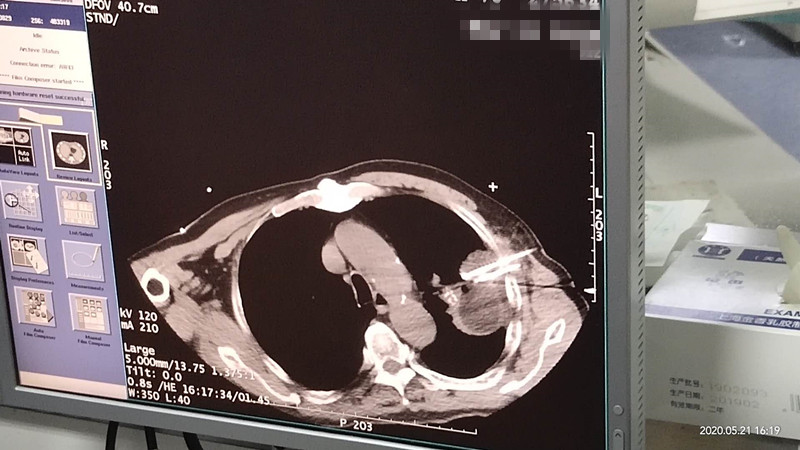

76岁肺部氩氦刀冷冻消融

发布人:美国氩氦刀技术官方网站    发布时间:2020/5/22 15:12:45